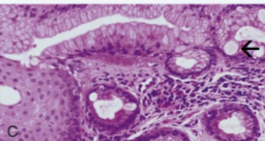

Metaplasia in the lower esophagus from squamous to intestinal type mucosa with goblet cells

Acid backwash into the esophagus (symptons of GERD) predisposes for Barrett’s

Increased RISK for the development of Esophageal Adenocarcinoma

Risk is significant if “pre-cancerous” Dysplasia is present

Barrett Esophagus